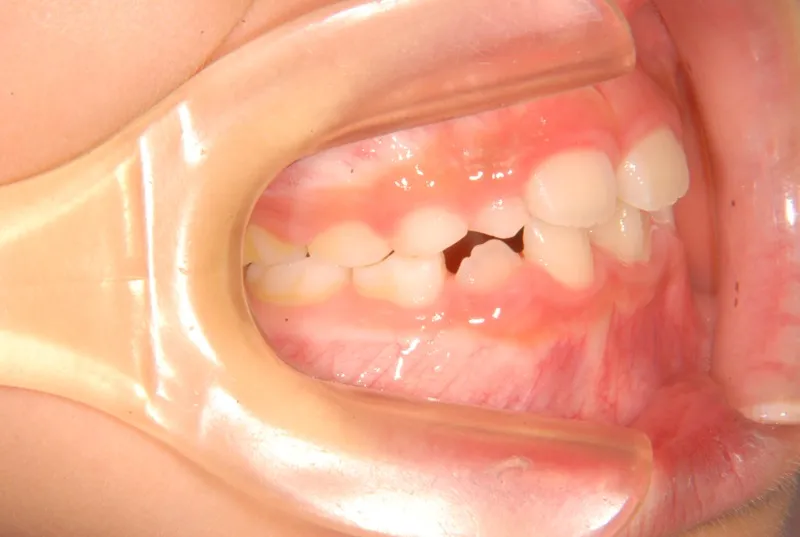

初診時年齢 小学校2年生 (男性) 主訴 癒合歯・永久歯が生えるスペースがない

診断名 叢生 装置名

上下の歯並びが狭く、永久歯の生える隙間がありません。

右下に癒合歯があり 上下の歯並びのアーチが悪くなっています。